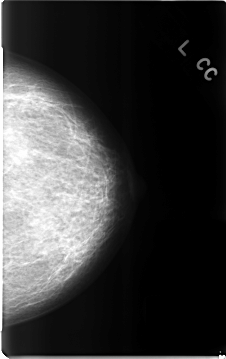

C_0311_1.LEFT_CC

LEFT_CC LINES 4664 PIXELS_PER_LINE 2936 BITS_PER_PIXEL 12 RESOLUTION 50 NON_OVERLAY